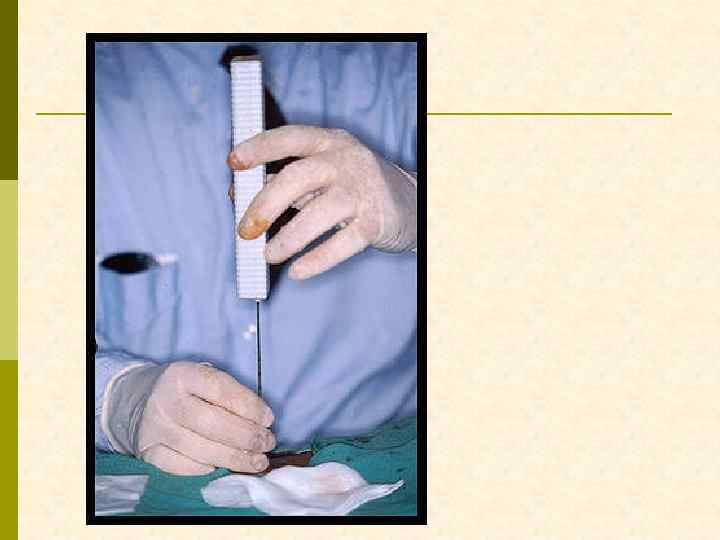

Кусочек, который изымается из почечной ткани при биопсии, соответствует длине и диаметру ложа пункционной иглы

ЧТО НУЖНО ДЛЯ ВЫПОЛНЕНИЯ ДИАГНОСТИЧЕСКОЙ НЕФРОБИОПСИИ? Биопсионная игла Vim-Silverman’a игла Tru-Cut игла с пружиной Аппарат ультразвуковой диагностики (с ультразвуковой поддержкой нефробиопсия выполняется быстрее, но частоту осложнений она не уменьшает) А также: шприц 10– 20 мл, игла для п/к введения анестетик (новокаин 0, 5% 20– 40 мл) игла инъекционная 100– 120 мм скальпель предметное стекло консерванты для биоптата (N 3 !!)

ВВЕДЕНИЕ БИОПСИОННОЙ ИГЛЫ В РЕТРОПЕРИТОНЕУМ